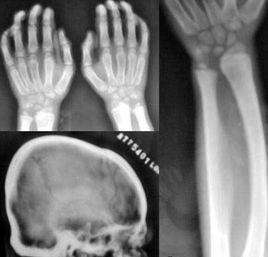

粘多糖病的臨床診斷根據其臨床表現、X線骨片的特點和尿中排出不同的粘多糖增多。甲苯胺藍呈色法可作為本病的篩查試驗,也可用醋酸纖維薄膜電泳來區別了中排出的粘多糖類型,並協助分型。各型MPS的確切診斷需測定白細胞或皮膚成纖維細胞特異酶的活性。各型粘多糖病大部分可進行羊水細胞cDNA基因分析作產前診斷。

根據臨床表現和X線骨片的改變,結合以下實驗室檢查可以診斷。①末梢血白細胞,淋巴細胞和骨髓血細胞中可見到異染的大小不等、形狀不同的深染顆粒,有時呈空泡狀,顆粒稱Reilly氏顆粒,經證實為粘多糖。②患者尿中排出大量酸性粘多糖,①可超過100mg/24小時(正常為3~25mg/24h),確診指標為證實尿中排出的為硫酸皮膚素和類肝素。患者白細胞,成纖維細胞或肝細胞和尿中缺乏α-艾杜糖醛酸酶。

Ⅳ型的臨床特點為明顯的生長遲緩,步態異常和骨骼畸形且逐漸顯著。骨骼的畸形表現和I-S型相似,脊椎的鳥嘴突,椎骨扁平,飄帶肋骨,還可有雞胸,骨質疏鬆,髂骨外翻,股骨頭變平,腕和膝關節腫大,但無關節強直。顏面呈頜骨突出,鼻矮,口大、牙間隙寬及牙釉質發育不良。學齡期出現角膜混濁,皮膚增厚且鬆弛。智力發育基本正常為Ⅳ型的特點。青春期發育可正常。逐漸出現脊髓壓迫症狀,晚期出現麻痹性截癱和呼吸麻痹。病人壽命多為20~30歲。

臨床重型表現多從2~3歲開始生長遲緩,關節活動嚴重受限,頸短,角膜混濁發生較早,顱骨蝶鞍呈鞋型,顱骨縫早閉合可引起神經系症狀,出現腦積水和痙攣性偏癱。骨骼畸形的程度個人間差異較大,逐漸發生骨骼畸形如I-H型上肢長骨受累比下肢重。可有肝脾腫大。智力正常,但可有眼失明和耳聾。心臟亦可有異常可引起死亡,壽命多不超過10歲。